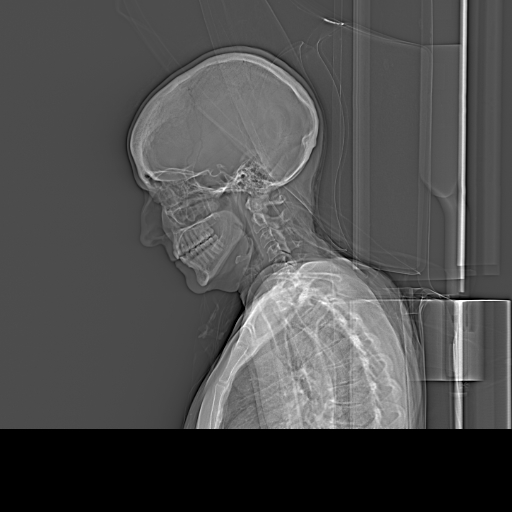

Thank you for welcoming me into this group. I am new. I have been in hell since 2023, but before that have had bizarre and bad symptoms since around 2016, but really bad since 2018: severe migraines and pain shooting into the left side of my face (one of the worst symptoms), neck pain, ears blocked and ringing in my ears, sinuses blocked and pressure, dizziness and vertigo, severe neck cracking, brain fog, vision problems (the other worst symptom) on the left side, pain around the ear, jaw pain and bite problems (teeth don’t touch at all in back suddenly for no reason), occasional numbness in the back of my head, trouble talking and fatigue talking (bad symptom), tongue fatigue and problems, throat issues, painful spot behind left upper molar area, and more. It’s been a hellscape. I do not know what is going on but my sister read about Eagle Syndrome, and then she and I both uploaded my X-rays into AI and it said they were elongated and prominent. If it’s not this, it’s my cervical spine, but my cervical spine MRI only shows “mild degenerative changes.” I am 57 years old and female. Most people my age would have mild degenerative changes. I have been to several doctors for the neck issue and most have said my cervical spine could not be responsible. But, one new one I saw recently said my spine IS causing my “headaches” but he did not say what part of my spine is responsible or how it is causing all of this. He just said “the pain is coming from your neck.” He wants to put Botox into my SCM muscles and if that does not work, do facet joint injections at C5, C6, and C7. I am not necessarily opposed to this, but my question is: Why? What evidence is this being based upon? The treatment seems to be just a shot in the dark. How long do I go on taking all kind of meds (been there, done that, to no effect) and letting all kind of docs do all kinds of scary procedures on me without knowing what is wrong?

Anyway I have two lateral X-rays taken in 2023 and 2024 when I went to the ER with severe pain and they ruled out stroke. Is anyone available to read them?